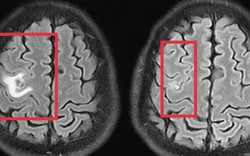

• Bác sĩ ung bướu nhắc nhở 5 việc phụ nữ nên làm ngay để giảm nguy cơ mắc ung thư

Bác sĩ ung bướu nhắc nhở 5 việc phụ nữ nên làm ngay để giảm nguy cơ mắc ung thư

Sức khỏe -

Dù nam giới vẫn là nhóm có tỷ lệ mắc ung thư cao hơn, song tốc độ gia tăng ca bệnh lại đang diễn ra nhanh hơn rõ rệt ở phụ nữ. Để phòng tránh, chị em nên làm ngay 5 việc này.